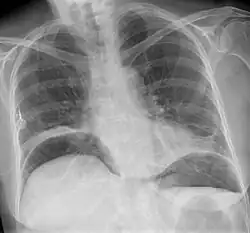

Freie Luft unter dem Zwerchfell bei Darmperforation

Die Diagnostik basiert auf der körperlichen Untersuchung und der Ultraschalldiagnostik. Bei Verdacht auf eine Darmperforation kann oftmals freie Luft in der Röntgenübersicht oder in der Computertomographie (deutlich sensitiver) nachgewiesen werden. Die Computertomographie kann darüber hinaus häufig die Ursache (z. B. Divertikulitis, Tumor des Dickdarms) identifizieren oder Komplikationen (z. B. Abszess, Fistel) aufdecken.